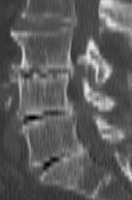

Diagnosis:Degenerative disk disease Discussion:The presence of a linear radiolucency in the disk space (vacuum phenomenon) is a typical finding of degenerative disk disease. It is often associated to other findings of degenerative disk disease such as disk space narrowing and endplate sclerosis. Gas in the disk space is rarely associated to disk space infection. References: